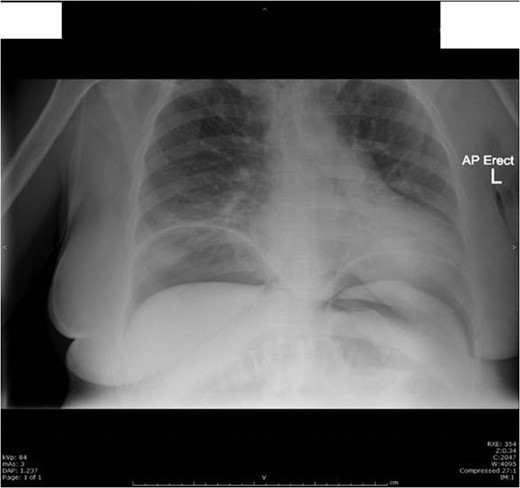

On Day 1 post surgery she was noted to be tachycardic, febrile and hypertensive with a drop in saturation 92–93% on room air along with abdominal pain. Her differential diagnosis included atelactesis, pulmonary embolism and endometriosis (Fig. 1). On examination she had good bowel sounds, was passing flatus but had not opened her bowels. On Day 2 she had localized right lower quadrant tenderness with raised inflammatory markers of CRP 163, WCC 21 × 109/l and neutrophil count 17 × 109/l. The computed tomography (CT) scan of her abdomen/pelvis (A/P) showed evidence of ileus with dilated loops of bowel (Fig. 2).

Day 1 postoperative chest X-ray shows evidence of mild atelactesis.